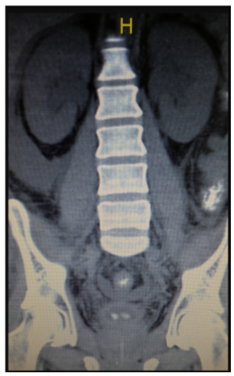

The Renal US revealed a dilated aspect of the kidneys, and bilateral ureteral and pyelocaliceal ectasia, with the presence of bilateral lithiasis in the ureteropelvic junction. CT scan confirmed both bilateral ureteropyelic ectasia (23mm) and lithiasic images (7.5 mm right kidney and 10 mm the left). There was a presence of dense material in both distal ureters. (Figure 1) The clinical picture was interpreted as obstructive AKI secondary to bilateral nephrolithiasis caused by HAART + Ganciclovir. A right double “J” catheter was inserted by cystoscopy; in the left ureter, a discharge of multiple small calculi was observed. Retrograde pyelogram did not show any obstructions at any level. The patient has discontinued Ganciclovir, and the treatment schedule was changed to include antiretroviral therapy without atazanavir. The patient developed post-obstructive polyuria, without hemodynamic or electrolyte abnormalities and he also showed a recovering normal renal function.

Figure 1 Abdominal CT Scan: Bilateral hydronephrosis.

Bilateral lithiasis in the ureterovesical junction.